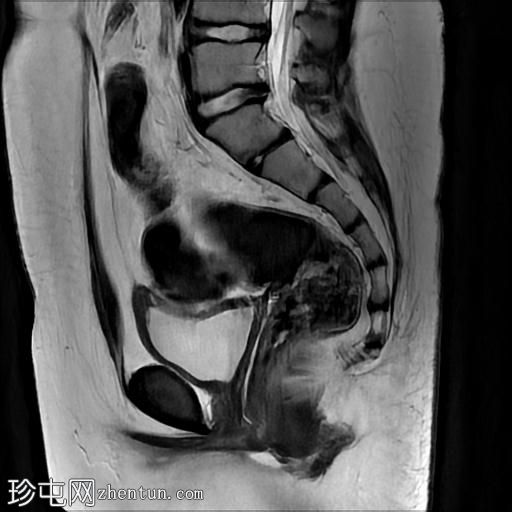

轴位

T2

MRI序列显示:

女性外生殖器

子宫、宫颈及阴道上2/3缺失

左侧睾丸及腹股沟管内环

右侧睾丸位于腹腔内,靠近腰大肌

双侧卵巢未显影

MRI结果提示雄激素不敏感综合征 (AIS),患者基因构成为男性,但外生殖器为女性(46XY核型)。由于细胞对睾酮等雄激素产生抵抗,雄激素不敏感综合征常伴有双侧隐睾。